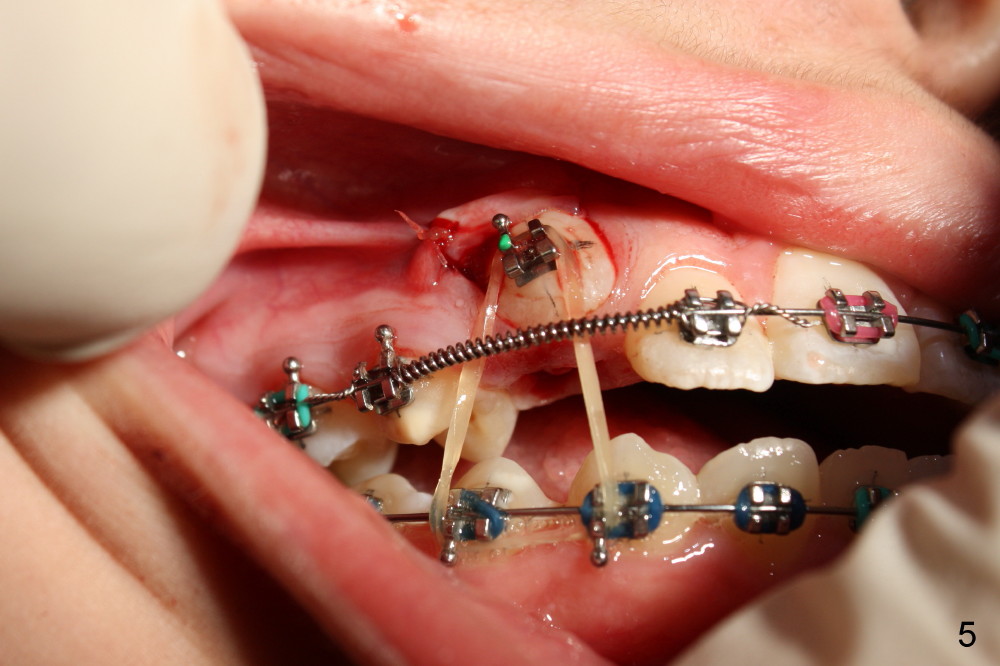

Two oblique incisions were made mesial and distal to UR3 (Fig.3). The mucoperiosteal flap (Fig.3 arrow; Fig.4 F) was raised and pushed apically for bracket placement. Following extraction of UR C, one-fourth inch elastics were placed between U3 and L3,4 (Fig.5,6). The patient was instructed to wear the elastics 24 hours per day. The upper wire is .018 ss with open coil springs, while lower .020.